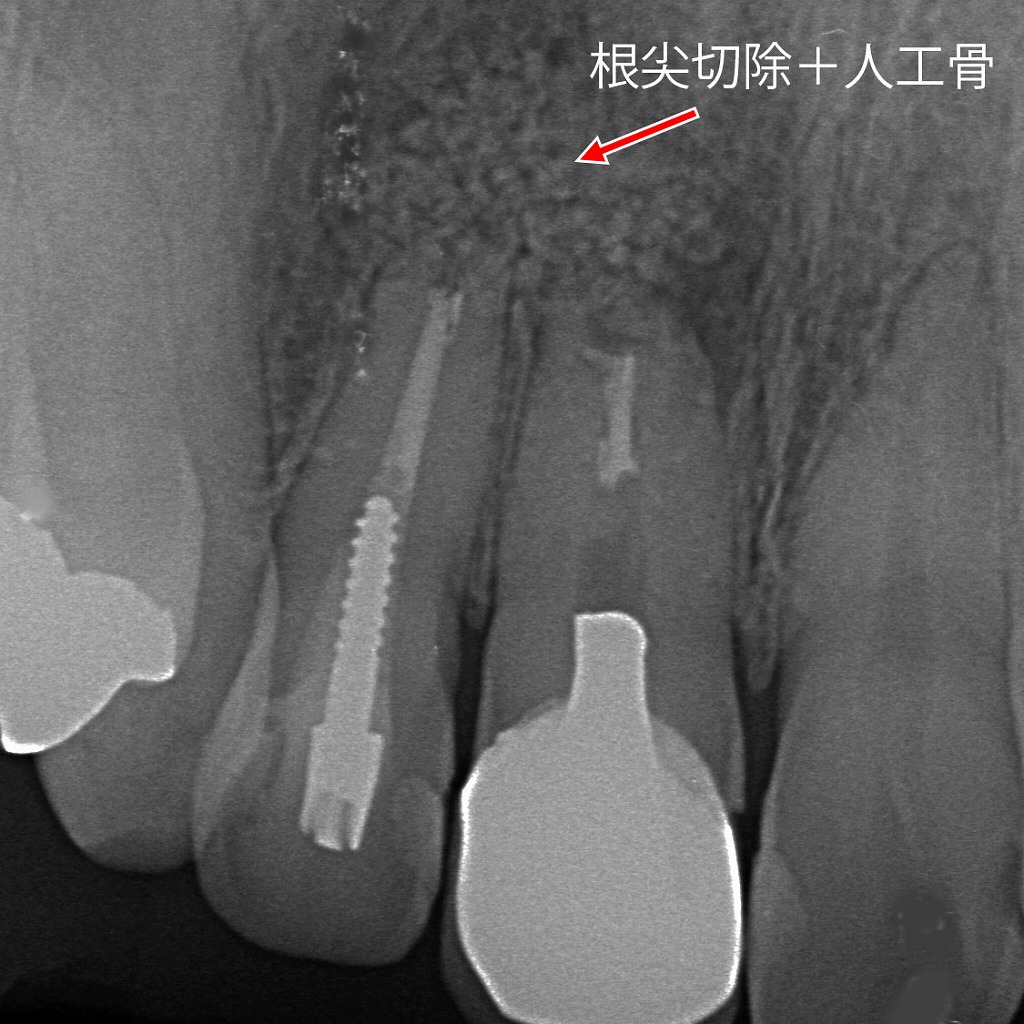

歯根端切除術+人工骨による病変治療

根管治療後も改善がみられなかった根尖部の病変に対し、歯根端切除術を行った症例です。感染源となる歯根の先端を切除し、病変を除去したうえで人工骨を填入しています。レントゲン上では、矢印部に人工骨が確認でき、骨の再生を促しながら歯の保存を図っている状態です。抜歯を回避するための外科的保存治療の一例です。

症例です。感染源となる歯根の先端を切除し、病変を除去したうえで人工骨を填入しています。レントゲン上では、矢印部に人工骨が確認でき、骨の再生を促しながら歯の保存を図っている状態です。抜歯を回避するための外科的保存治療の一例です。